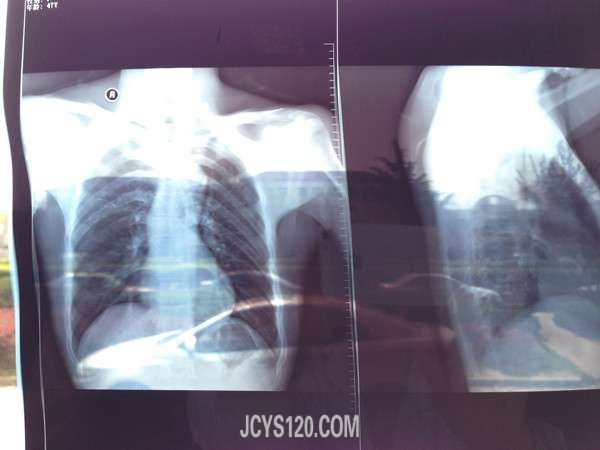

患者自述,两年前无诱因出现左下胸部麻木感伴闷痛,无呼吸困难咳嗽咳痰及咳血,未诊治,两年来病情时好时坏,因能耐受且工作忙绿一直未做任何治疗。近一个星期来,患者感左下胸部麻木感加重,闷痛感不明显。来诊。患者自发病以来,精神情绪饮食睡眠及二便正常。

T36度 P81次/分 R18次/分 BP 125 / 85MMHG 中年男性,神清,自主体位查体合作。胸廓无畸形,双肺呼吸音清,无干湿罗音,叩诊呈清音左下肺无叩击痛。心率81次/分律齐。无病理杂音。腹软,未见肠型及蠕动波,左上腹部无压痛反跳痛。肾区无叩击痛,墨菲氏征(—)肝区无叩击痛,麦氏点压痛(—),余(—).

肋间神经炎?

泌尿系统结石?

左下肺 炎症 ?

因诊断不明,嘱患者去医院进一步检查,资料如下,

因未确诊疾病,上级医院医生让患者继续观察。由于麻木感明显,我按照肋间神经炎给予患者消炎活血止痛药物口服。观察。在未确诊的情况下,该患者治疗方向应该怎么走?请大家帮助诊断、治疗、谢谢。